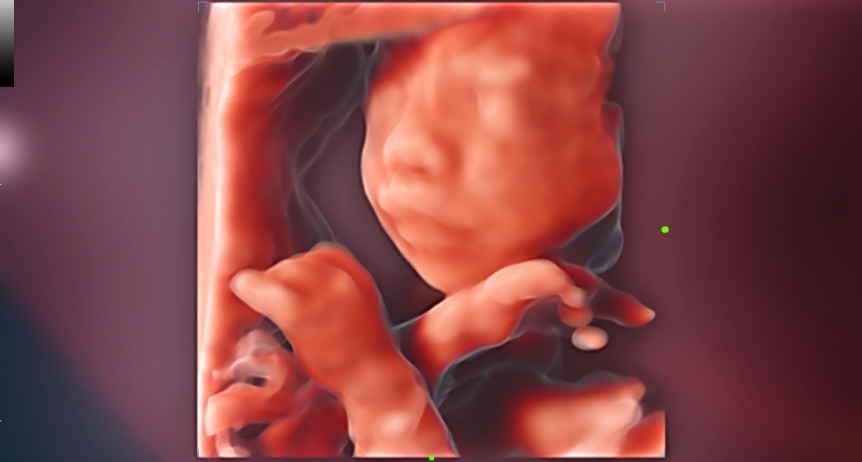

ROSTRO FETAL iLive